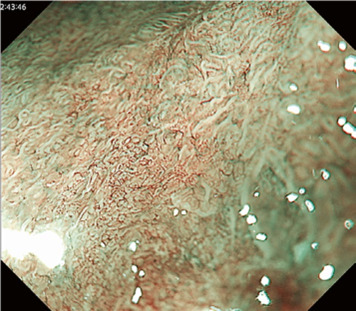

Predicting invasion depth of superficial esophageal squamous cell carcinoma is crucial in determining the precise indication for endoscopic resection (ER) because the rate of lymph node metastasis increases in proportion to the invasion depth of the carcinoma. Previous studies have shown a close relationship between microvascular patterns observed by magnifying endoscopy and invasion depth of the superficial carcinoma. Although there were two major classifications, Inoue and Arima, the Japan Esophageal Society (JES) integrated the two classifications and simplified it and developed a new magnifying endoscopic classification for the characterization and predicting invasion depth of superficial esophageal squamous cell carcinomas (SESCCs). This is essential for developing a treatment strategy for SESCC, in particular the indication for ER. Therefore, in this classification, morphological types of microvessels are classified into two categories of noncancerous [type A: normal epithelium, inflammation, and squamous intraepithelial neoplasia (SIN)] and cancerous (Type B: SCC) lesions. The cancerous types of microvessels corresponding to SESCCs are subclassified into three groups based upon an indication for ER as follows: an absolute indication type (Type B1: T1a-EP or T1a-LPM), a relative indication type [Type B2: T1a-MM or T1b-SM1(tumor invades the submucosa to a depth of 200 μm or less from the muscularis mucosa)], and a contraindication type [Type B3: T1b-SM2 (tumor invades the submucosa to a depth more than 200 μm)]. Diagnostic criteria of the JES classification are based on the degree of microvascular irregularity in the target lesion observed by magnifying endoscopy. Intrapapillary capillary loops (IPCL) are a basic unit of microvasculature in the stratified squamous epithelial layer. The microvascular irregularity is evaluated for the presence or absence of each of the following morphological factors: weaving (i.e., tortuosity), dilatation, irregular caliber, and different shape (i.e., various shapes). Microvessels are classified as type A if they have three or fewer factors (i.e., without severe abnormality; . Fig. 1a) and type B if they have all four (i.e., with severe abnormality). Type B is then subclassified into B1, B2, and B3 (. Fig. 1b–d, respectively) based on the running pattern or degree of dilatation of severely irregular microvessels. The definitions and schemas of type A and B vessels and predicted histology of invasion depth by type B vessels are summarized in . Table 1. A large scale validation study showed high overall accuracy (90.5%) of type B vessels of the JES classification. The most important auxiliary criterion in the JES classification is avascular area (AVA). AVA is defined as a low or no vascularity area surrounded by all subtypes of type B microvessels including B1 vessels. Diameters of AVA are positively correlated with sizes of histological cancer nest and the histological invasion depth of SESCC. Small (<0.5 mm), middle (0.5 ≤< 3 mm), and large (≤3 mm) AVA are suggestive of T1a-EP/ LPM, T1a-MM/T1b-SM1, and T1b-SM2, respectively. A key point to note is that any types of AVA (small, middle, and large) surrounded by B1 vessels are suggestive of T1a-EP or T1a-LPM SCC.